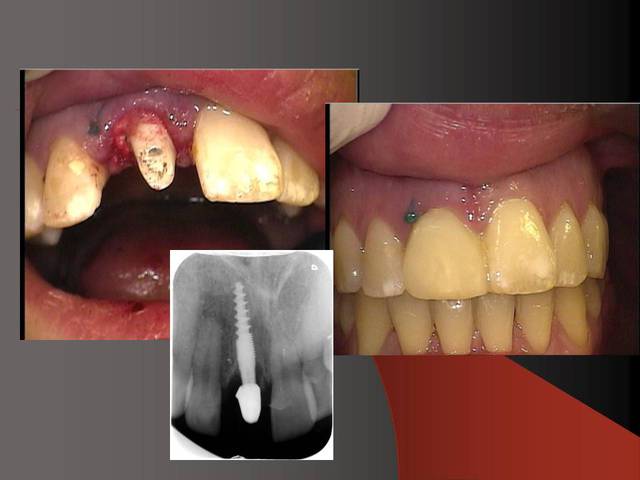

J´ai mis des photos pour mieux voir....

Merci pour ta remarque.C´est vrai que cela est mieux si on ne prérare pas ou presque pas les prep cap à cause des shippings . Normalement je ne les prépare pas, je choisis une forme (avec angle et longueur diiférents) selon le cas et ensuite je les cémente.

Sur la photo 5 on voit que je prépare surtout le titane de l´implant, le titane ne donne pas beaucoup du chaud quand il est préparé avec l´eau (pas comme aluminium par exemple).

Photo 2 du dernier cas, je crains beaucoup pour la plaque d'os en vestibulaire, même en flapless.